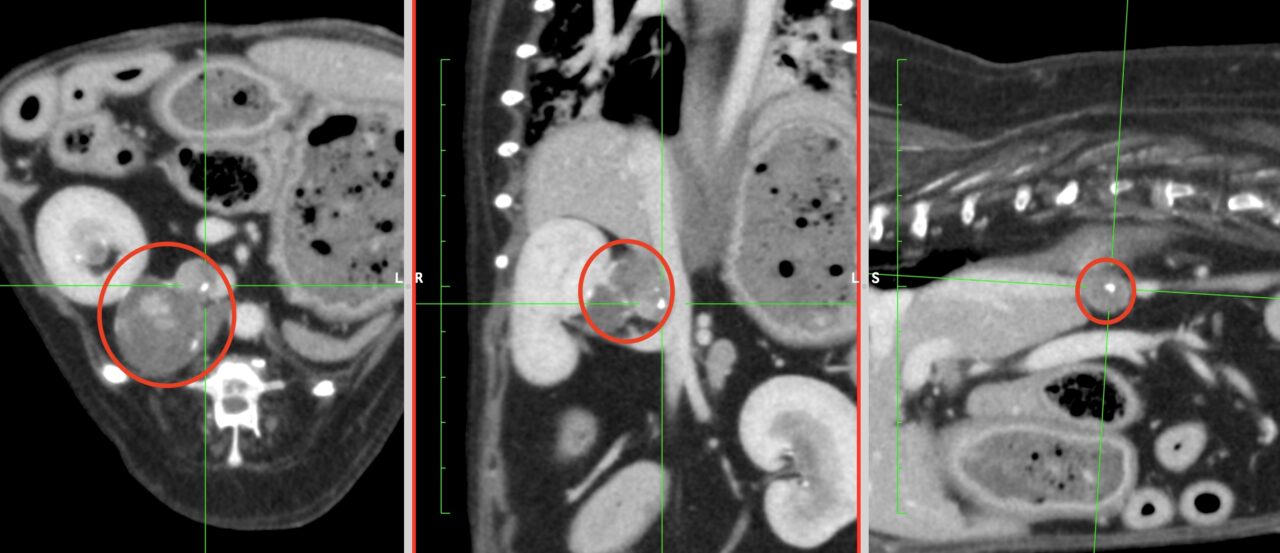

副腎皮質腺癌のCT画像(赤丸)

画像検査(エコー検査やCT検査)では確定することはできませんが、副腎皮質腺癌を疑うことは可能です。

・CT検査:がんの大きさや広がり、リンパ節転移、遠隔転移(肝臓、肺など)の評価

※CT検査はより綿密な治療方針を決定するうえで必須の検査です